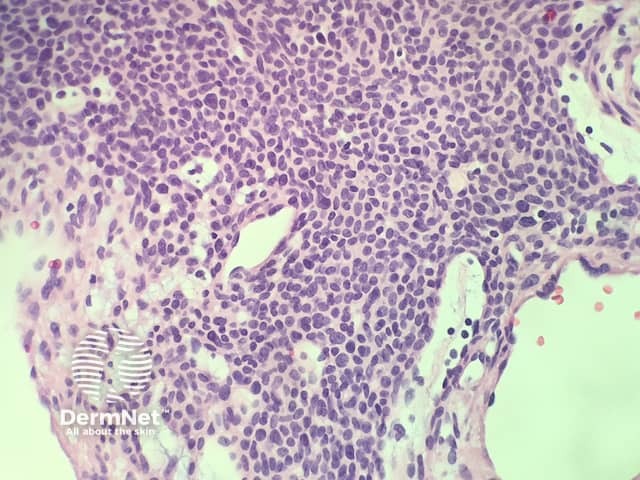

In glomangioma, the histopathology shows dilated venous channels that resemble venous malformations (figures 1, 2). Unlike venous malformations, they demonstrate single to multiple rows of surrounding cuboidal glomus cells (figures 3,4).

Figure 3

The glomus cells stain positively for vimentin and α-smooth-muscle actin but are negative for desmin, von Willibrand factor, and S-100.